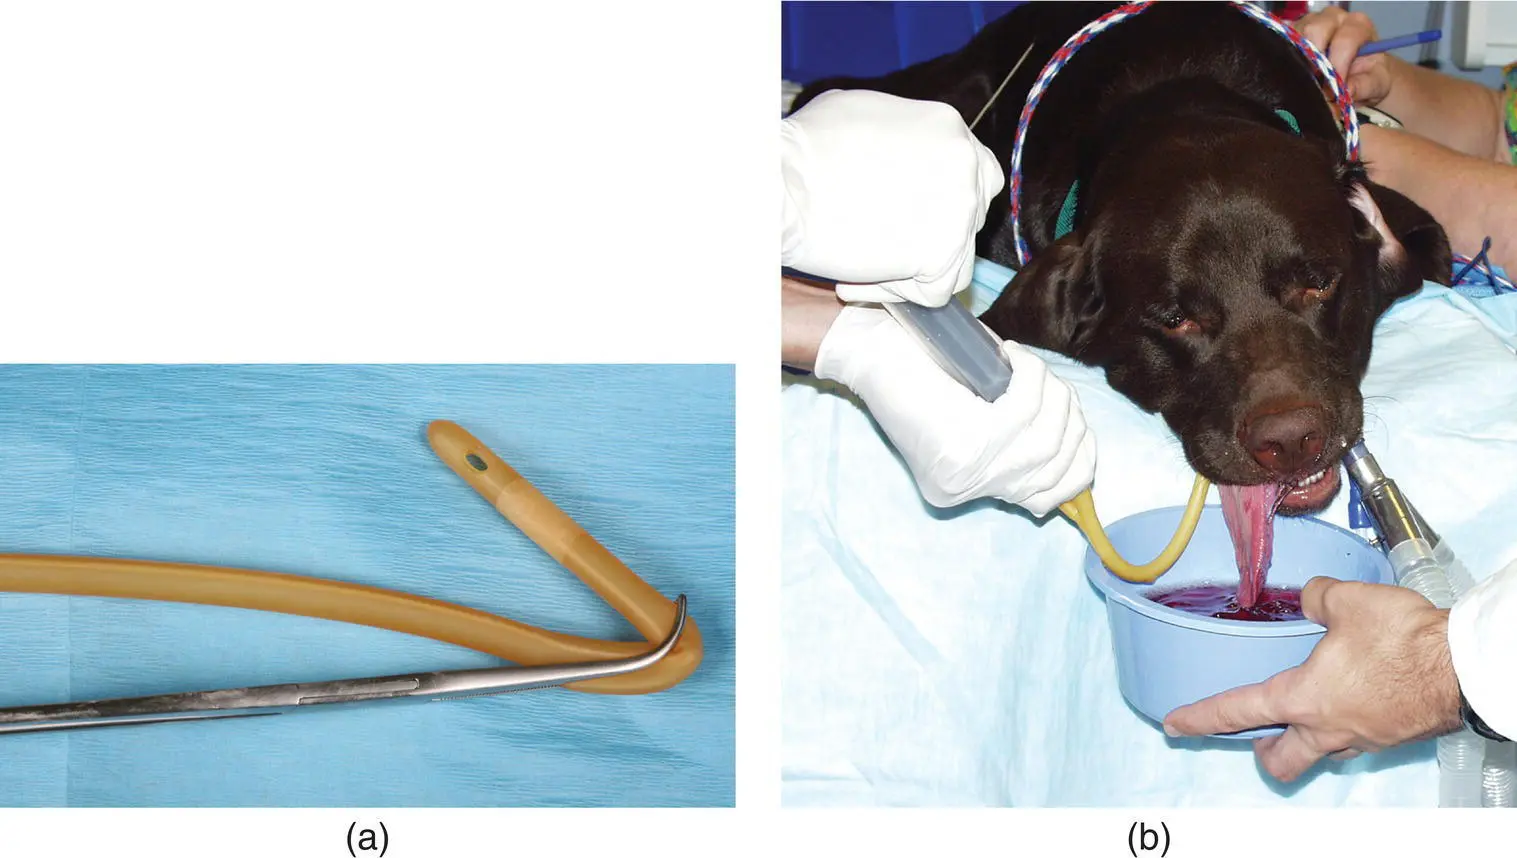

Figure 2.15 (a) Right‐angle forceps can be used to place a Foley catheter above the soft palate. (b) The forceps with Foley are inserted into the oral cavity and a spay hook can be used to retract the palate over the balloon portion of the Foley. The balloon is fully inflated and nasal flush can be used to dislodge foreign material or exudate into a collection bowl.